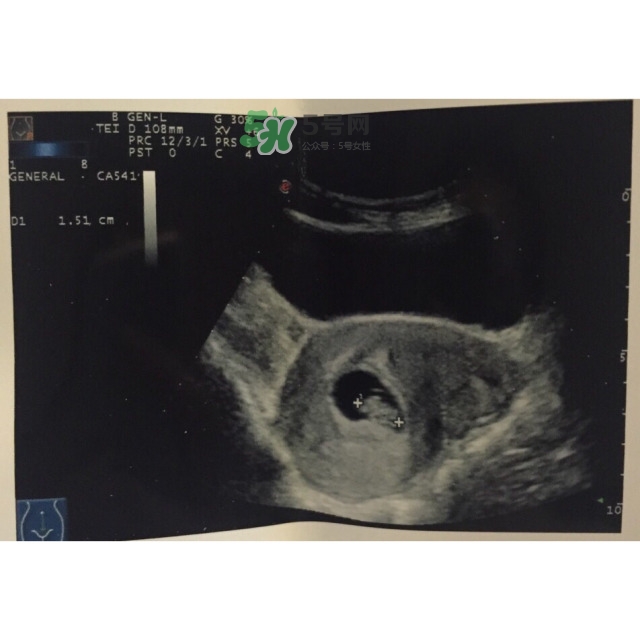

第一次做B超,胎兒太小,只見(jiàn)孕囊,未見(jiàn)卵黃囊和胚芽

第二次做B超,已見(jiàn)卵黃囊和胚芽

關(guān)于B超(簡(jiǎn)稱(chēng)BC)其實(shí)沒(méi)有媽媽們想的那么可怕,我的醫(yī)生朋友說(shuō),BC檢查探頭不要長(zhǎng)時(shí)間停留在一個(gè)位置,不是每天都做,對(duì)寶寶幾乎是沒(méi)有影響的。BC的輻射比你天天對(duì)著電腦、電視、手機(jī)遠(yuǎn)遠(yuǎn)小的很多,不會(huì)導(dǎo)致胎兒畸形哦。